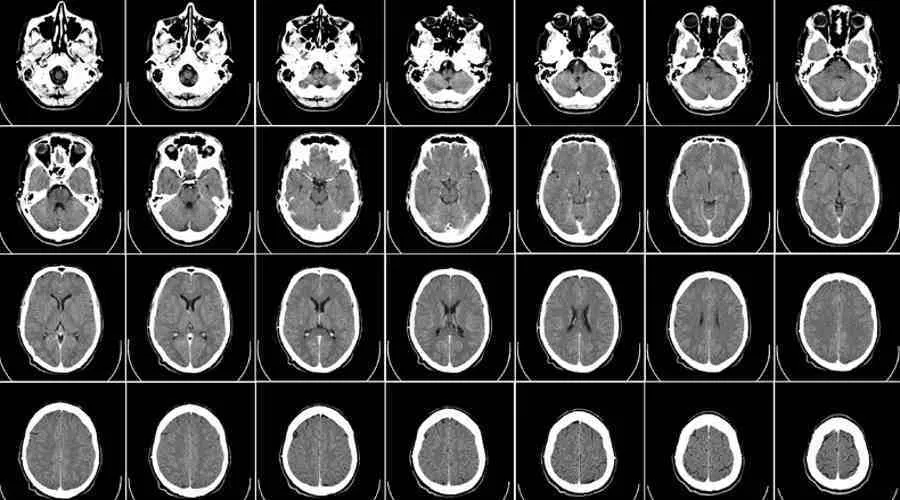

Rezonans magnetyczny głowy to niezwykle precyzyjna technika obrazowania, która wykorzystuje silne pole magnetyczne i fale radiowe do tworzenia szczegółowych obrazów struktur anatomicznych mózgu. Na obrazach MRI lekarz jest w stanie zwizualizować z wysoką dokładnością tkanki miękkie, naczynia krwionośne, płyn mózgowo-rdzeniowy oraz wszelkie zmiany strukturalne, takie jak guzy, torbiele, obszary uszkodzeń po udarach czy ogniska demielinizacyjne. Ważne jest, aby zrozumieć, że MRI pokazuje nam fizyczną architekturę mózgu. Nie jest to jednak narzędzie, które bezpośrednio "widzi" nasze myśli, emocje, wspomnienia czy samą chorobę psychiczną w sensie jej psychologicznego podłoża. Widzimy natomiast zmiany strukturalne, które mogą być z nimi skorelowane.Dlaczego psychiatra może skierować Cię na rezonans? Kluczowa rola diagnostyki różnicowej

Rezonans w walce z organicznymi przyczynami objawów psychicznych: Co wyklucza MRI?

Udary mózgu, nawet te "nieme", czyli przebiegające bez wyraźnych objawów neurologicznych, mogą pozostawić trwałe ślady w mózgu. Podobnie przewlekłe zmiany naczyniowe, wynikające np. z miażdżycy czy nadciśnienia, prowadzące do niedokrwienia mózgu, mogą być przyczyną powolnego, ale postępującego pogorszenia funkcji poznawczych, depresji, apatii, drażliwości czy innych objawów psychicznych. MRI jest niezwykle skuteczne w wizualizacji tych zmian. Pozwala na ocenę rozległości uszkodzeń po udarze, identyfikację obszarów niedokrwienia oraz ocenę stanu naczyń krwionośnych. Wykrycie takich zmian jest kluczowe, ponieważ objawy psychiczne mogą być pierwszym sygnałem problemów naczyniowych, które wymagają leczenia neurologicznego, a nie wyłącznie psychiatrycznego.